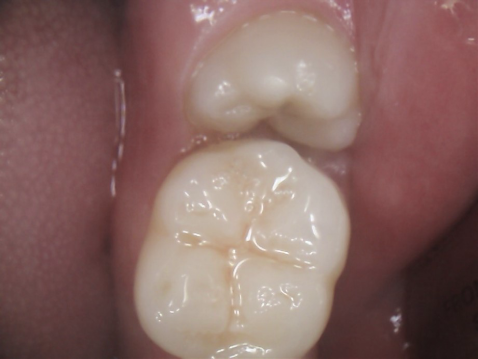

2.親知らずが虫歯になると、その手前の歯も虫歯になる可能性があります

一番右奥の親知らずは良く磨けず、虫歯になることが多いのです。早く抜いて、前の歯が虫歯にならないようにしなければなりません。

同じ症例をレントゲン写真で見たところです。親知らずが横倒しに生えていて、周りの骨を溶かしてしまっています。